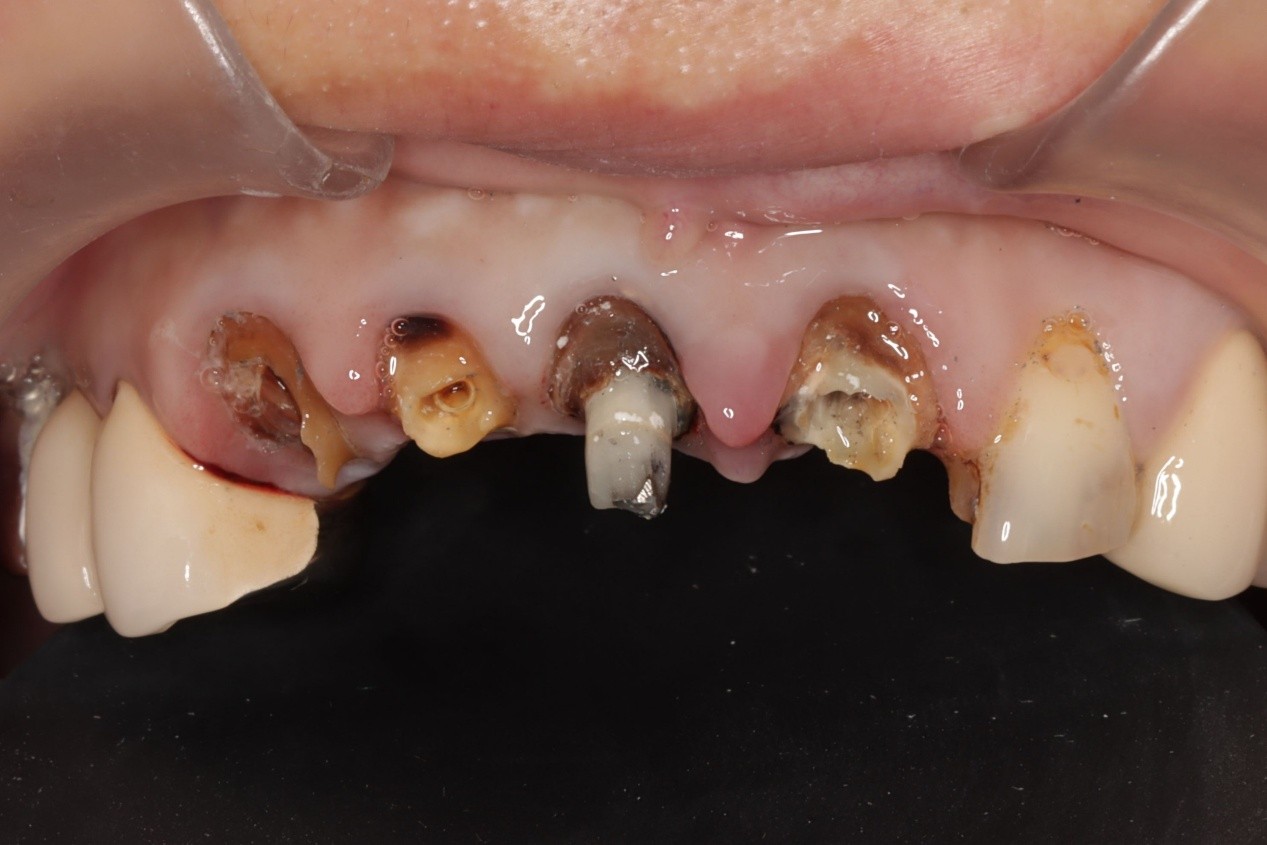

植牙是現今能在外型及功能上高度取代原生牙齒的治療方式之一,但人體神經元、血管絲小得可能只有只有微米大,比頭髮絲一半還細小,肉眼難以辨別那麼小、密密麻麻、且不時移動的影像,因此手術時要不傷到很困難,而口腔環境潮濕,往往術後癒合、療程效果都較不理想。

還好近年有了精準微創植牙手術,醫師可以透過更新的科技追蹤肉眼無法看到的位置,達到微創植牙,幫助病患快速癒合,建立幾乎與原生牙齒無二的體驗,從齒找回笑容。

安適準導航植牙系統可以於植體製作前(術前)做第一次植牙流程規劃,判讀病患牙齒間狀況,並做出最合適的植牙療程建議。搭載高達12顆鏡頭,於手術間幾乎零死角定位植牙位置,配合AI高速運算,讓植體精準的植入齒骨,創造幾乎與原生牙齒無二的舒適感。